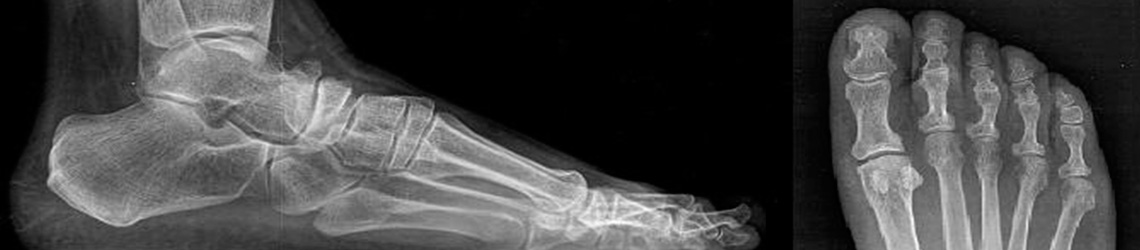

La radiología del pie y tobillo complementa a la exploración clínica, pues nos permitirá en el momento de la consulta, obtener una imagen radiológica del pie, la cual a su vez nos ayudará en la confirmación o descarte de la patología existente en ese momento. En la actualidad, la radiología digital permite obtener imágenes en formato digital sin necesidad de recurrir al tradicional revelado de “placas”